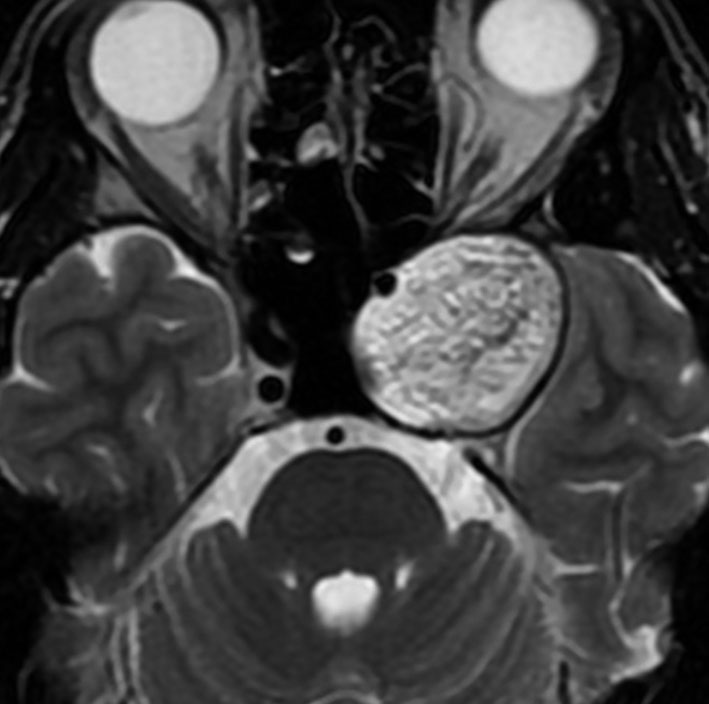

7歳の時に偶然発見された左海綿静脈洞外壁の類皮のう胞 dermoid cystで,多数の脳神経と皮膜が癒着するものです。この腫瘍は先天性の腫瘍なのでおそらく生まれた時からあったものです。10歳の時に手術摘出しました。画像は22歳の時の手術前のものです。何故2回も部分摘出したのかは,この類皮のう胞というのは脳組織や髄膜や脳神経にベトベト癒着してくっつく性質があるからです。海綿静脈洞内にある脳神経と剥離できませんでした。でも初回手術から12年無症状でしたし,2回目の手術後も無症状です。

左側の画像はガドリニウム増強のT1強調MRIです。壁が厚いと造影剤で増強されることがありますが,この壁はとて硬いです。

時には毛が生えていてゴムのように硬い鳥皮のようなものもあります。そういうのは周囲組織を損傷しないと剥がせません。

この画像は拡散強調画像 DWI と言います。左が術前,右が術後です。拡散強調画像 DWIで強い高信号になるのが特徴です。しかし,類表皮のう胞でも高信号になるので注意を要します。

のう胞壁を残したので,さらに5年後に急速に大きくなりました。本人も27歳になり,仕方がないのでよくよく相談して,のう胞ごと全摘出しました。これで治った,と思える手術です。たくさんの脳神経に癒着していました。でも幸い,大ごとにはならなくて,額の感覚が少し低下,左目から涙が出ない,左のまぶたが少し下がっている(軽度の眼瞼下垂)くらいですみました。通常は左目の機能を完全に失う手術です。